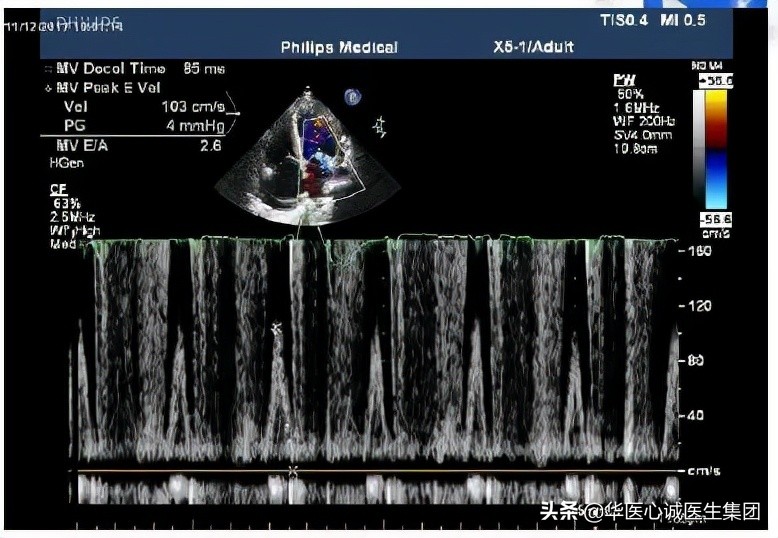

舒张功能的情况如何?E峰又高又尖,A峰很小,提示限制性充盈障碍。